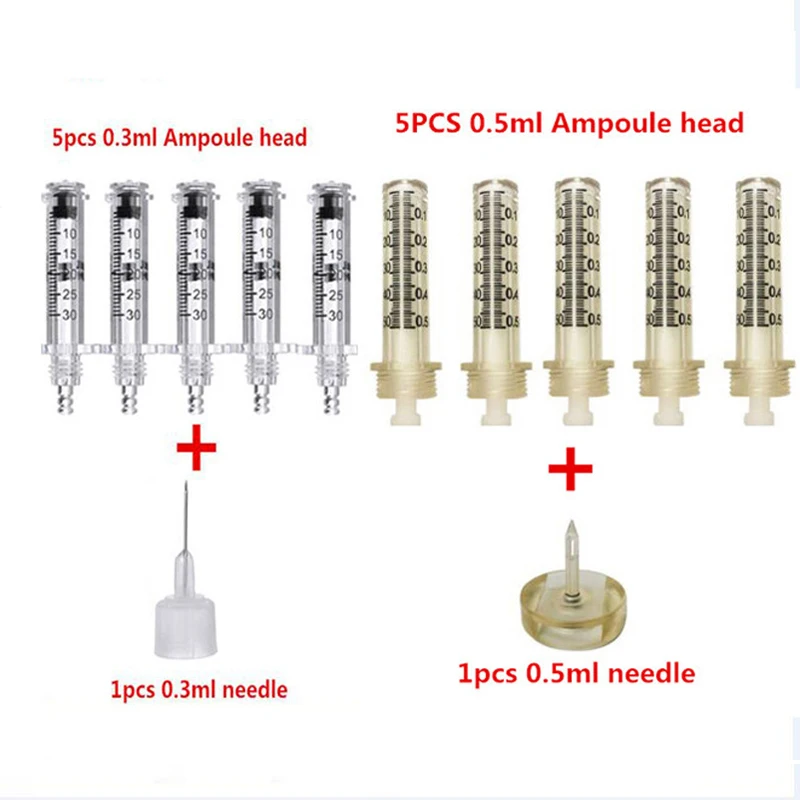

$19.21

Одноразовый шприц 0,5 мл/0,3 мл, ампула, стерипосылка, без иглы, наполнитель для губ, шприцы для гиалуроновой ручки

aliexpress.ru